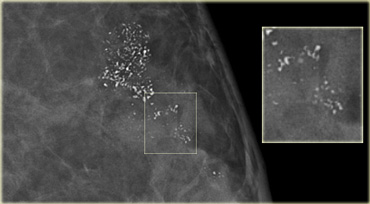

Magnified view: fine pleomorphic calcifications in a linear distribution.  Biopsy: High grade DCIS Magnified view: fine pleomorphic calcifications in a linear distribution. Biopsy: High grade DCIS

On the left fine pleomorphic calcifications in a segmental and linear distribution.

These were classified as BI-RADS 4B.

Biopsy revealed high grade DCIS.